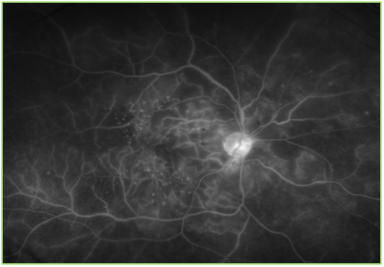

Due to concurrent chemotherapy treatments, the patient was not able to make it to his follow up. He finally presented 6 months later in April 2013, when his vision had reduced to 20/80 OD and OS. At this time, his left APD optic nerve was pale, macular edema was noted in OD and the retinopathy was still present OU. Fluorescein angiogram ordered at that time also showed marked capillary non-perfusion in both eyes, predominantly in the posterior pole region OD. Pan retinal photocoagulation was recommended at this time, however, it was contraindicated due to poor patient cooperation and limited cognitive abilities (Figure 1&2).

Figure 2 Optos image of the fluorescein angiogram of the right eye. Focal laser scars, microaneurysm, hemorrhages and marked capillary non-perfusion can be noted, especially in the posterior pole.